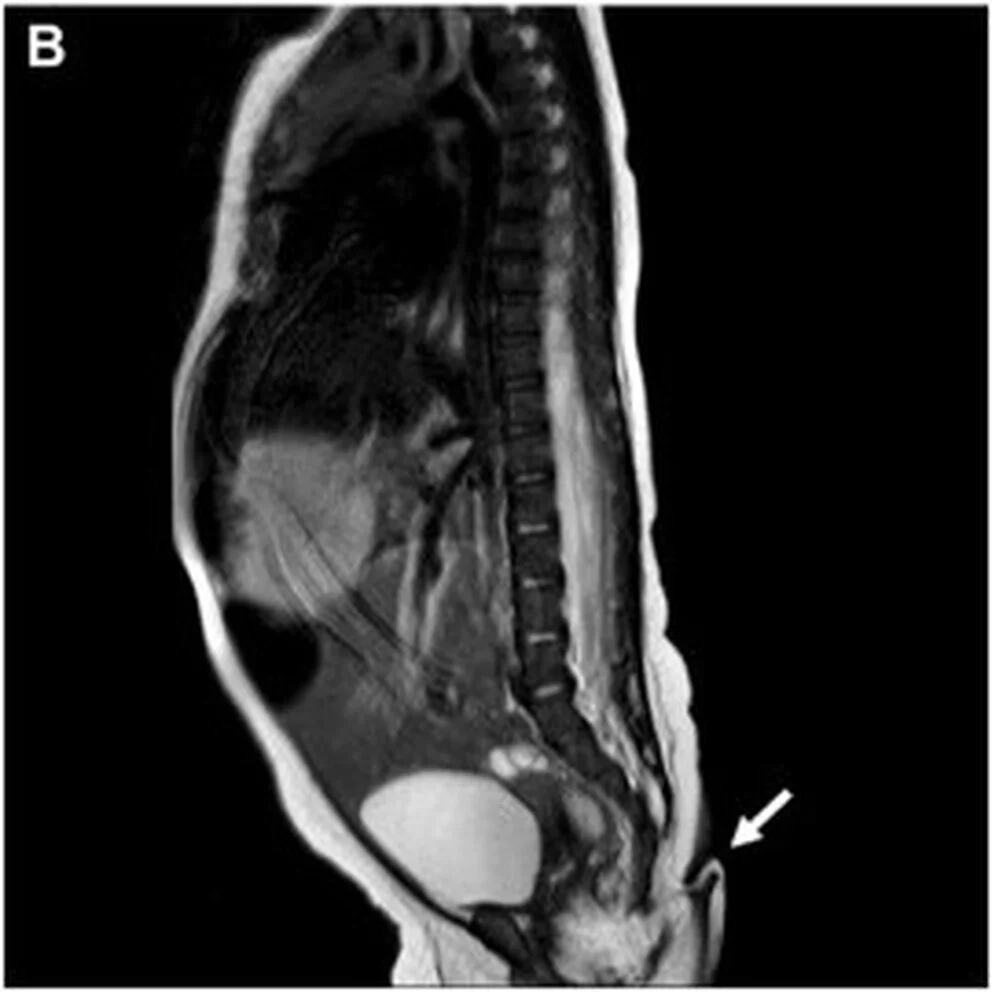

Tras el hallazgo, los médicos le aplicaron diversas pruebas a la bebé con cola:

- Una resonancia magnética, para identificar anormalidades cerebrales

El estudio subraya que los resultados de todas las pruebas descartaron irregularidades, por lo que la bebé con cola fue calificada como sana y dada de alta para seguimiento ambulatorio.